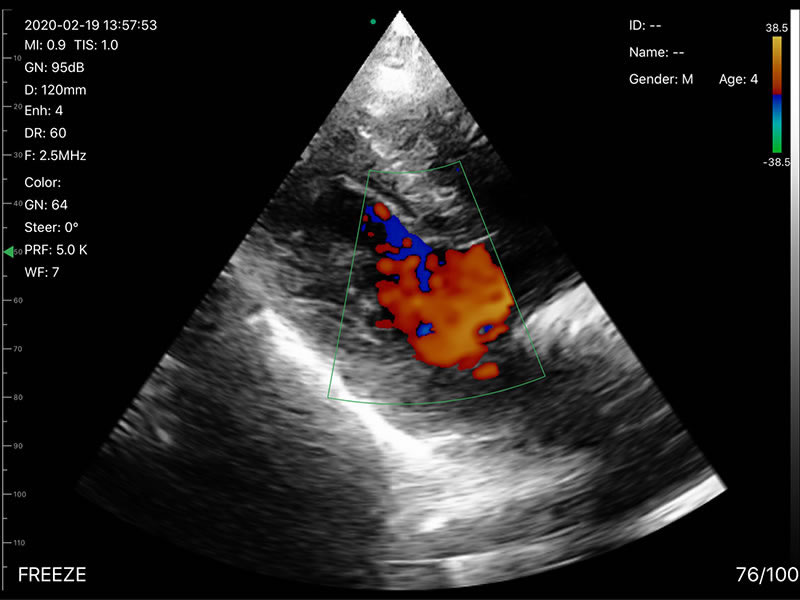

• Frequency: R60 Convex/Phasedarray probe 3.2MHz/5MHz,

• Scan angle and width: convex 60°, Phasedarray 80°, linear 40mm